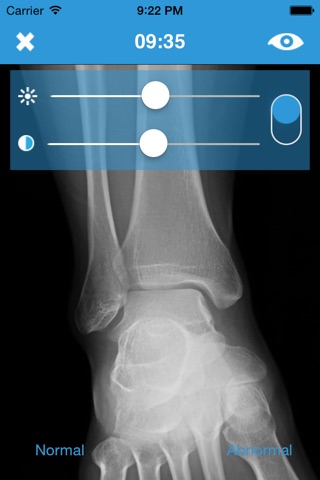

Each packet offers the opportunity to test your knowledge of x-ray anatomy and pathology, and to identify whether an image has normal appearances or abnormal appearances. Each test is set with a 5-minute countdown timer, allowing you enough time to peruse each image and use the image manipulation controls (zoom, brightness, contrast, inverse) to further analyse each one.